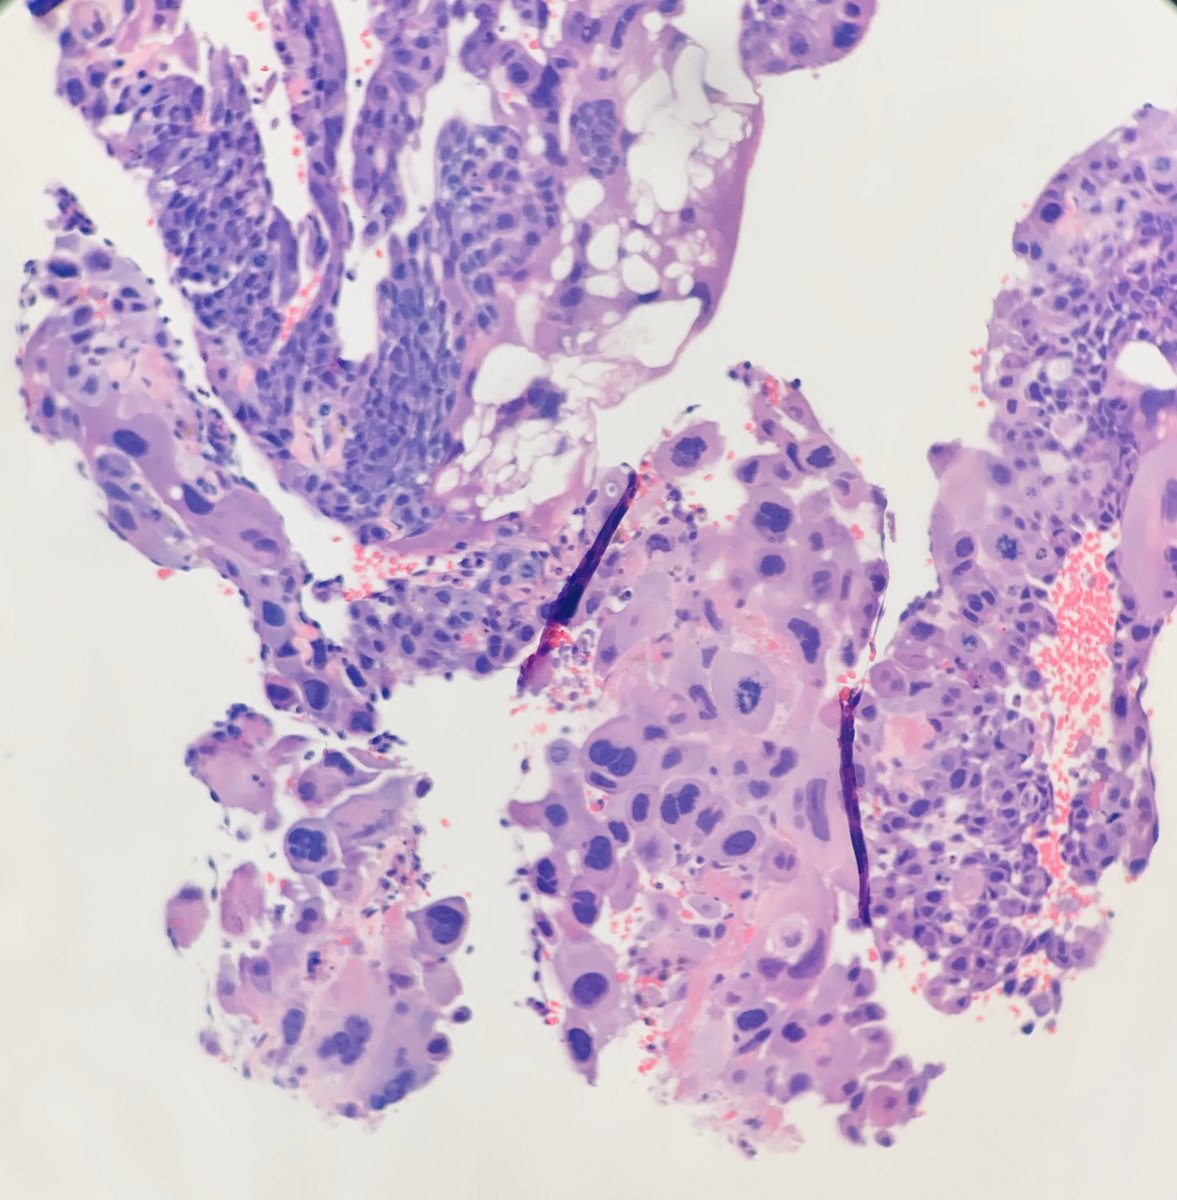

Few classic images of endocervical adenocarcinoma in situ

hrHPV In 80-90%

HPV type 18 > 16 > other

Tx: Usually cone/LEEP

HPV-associated features:

Apical mitoses and apoptotic bodies

Diffuse p16 IHC

Morphologic variants exist!

#OnePathboardPointAtAtime pic.twitter.com/UTCuXoPNdp